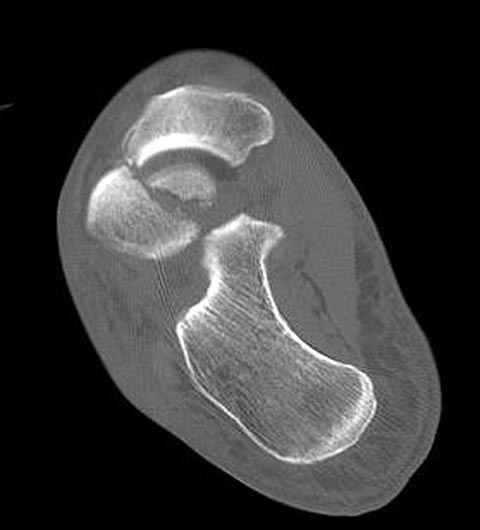

Уважаемые участники русского Ортофорума, поздравляю всех со всеми прошедшими праздниками: Новым годом, Рождеством, Hanukkah, Kwanzaa, желаю участникам всего наилучшего и здоровья.Повреждение таранной кости.Больной 81г автоавария, повреждение таранной кости, здесь снимки. Какие рекомендации?Djoldas Kuldjanov, MDDepartment of Orthopedic SurgerySt. Louis University Medical Center

Вдогонку по поводу перелома таранной кости, больная 81, не страдает диабетом, перелом закрытый, в первый же день поступления ограничились временным наружным фиксатором (как на снимке).

Планировалась открытая фиксация после спадения отека, но больная пожелала лечиться по месту жительству в другом штате..

Из-за отека на стопе тактика лечения у всех была

одинаковая: временная наружная фиксация до спадения отека, при изолированных переломах они выписывались домой и через дней 7 госпитализировались на оперативное лечение.

Примеры на снимке...